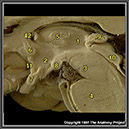

N2A1P1

31